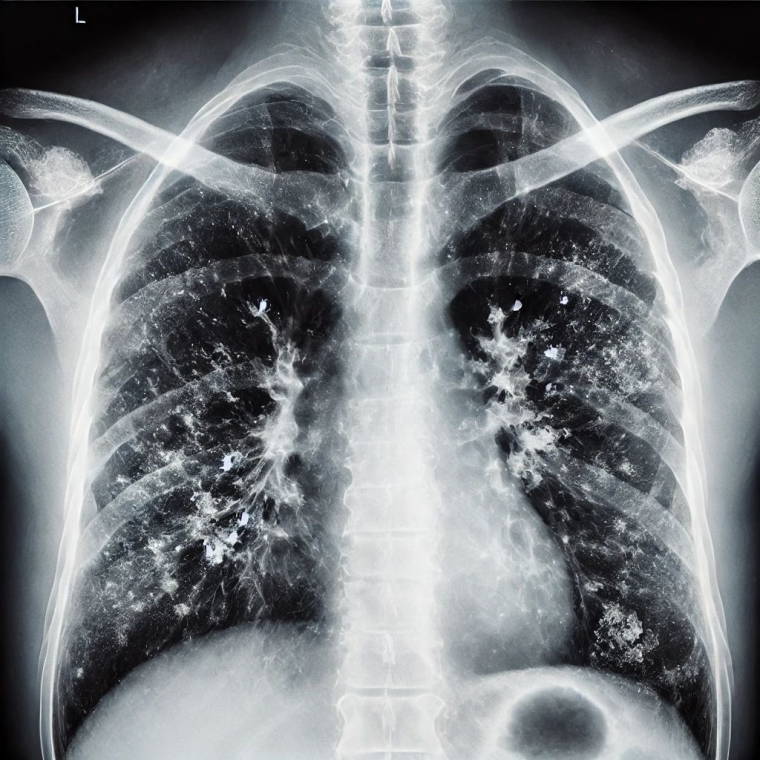

Zatürrenin grip ya da soğuk algınlığıyla karıştırılabileceğini belirten Prof. Dr. Özlü, "Bu tür enfeksiyonlar genelde üst solunum yollarında yerleşir. Oradan başlar ve nezle, soğuk algınlığı, farenjit, sinüzit gibi üst solunum yolu enfeksiyonlarına yol açar. Bazen de alt solunum yollarına ilerleyerek bronşit, bronşiolit gibi hafif hastalıklara yol açabilir. Fakat zatürre, bu hastalıklar arasında en ağır olanıdır. Maalesef, şu sıralar pek çok hasta zatürreyi fark edemiyor ve teşhiste geç kalıyor. Oysa zatürrede erken tanı çok önemli. Hekimin, 4 saat içinde doğru tedaviye başlaması, zatürreye bağlı ölümleri anlamlı şekilde azaltıyor" ifadelerini kullandı.

Zatürre tanısında en önemli belirtilerin nefes darlığı ve öksürük olduğunu ifade eden Özlü, "Şikayetleriniz tedaviyle ya da tedavisiz olarak ilk birkaç gün içinde azaldıktan sonra tekrar ikinci bir atak yaşanıyorsa; ateşlenme ve şikayetlerde artış oluyorsa bu da zatürrenin eklendiğini gösterebilir. Nefes darlığı çok önemli bir belirti. Özellikle nefes alıp vermekte zorlanıyorsanız, özellikle bebeklerde ve yaşlılarda solunum sayısının dakikada 24'ün üzerine çıkması, nefes alıp verirken hırıltı olması, bebeklerde burun kanatlarının solunuma eşlik etmesi, nabız sayısının dakikada 120'nin üzerine çıkması gibi durumlar zatürre olasılığını güçlendirir. Öksürük de önemli bir belirti. Zatürrede öksürük genellikle yaş öksürüktür. Yani balgamlıdır. Balgamın koyu renkli olması; kahverengi, koyu sarı, koyu yeşil gibi ve kıvamlı olması zatürre ihtimalini artırır. Ateşin çok yüksek olmasıyla birlikte yan ağrısı dediğimiz, öksürürken ya da nefes alırken batıcı şekilde hissedilen bir yan ağrısı varsa, bu da zatürreye işaret edebilir" dedi.